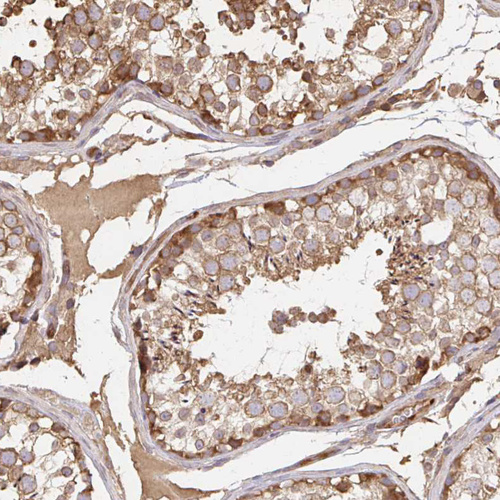

Immunohistochemical staining of human breast shows strong membranous and cytoplsmic positivity in glandular cells.